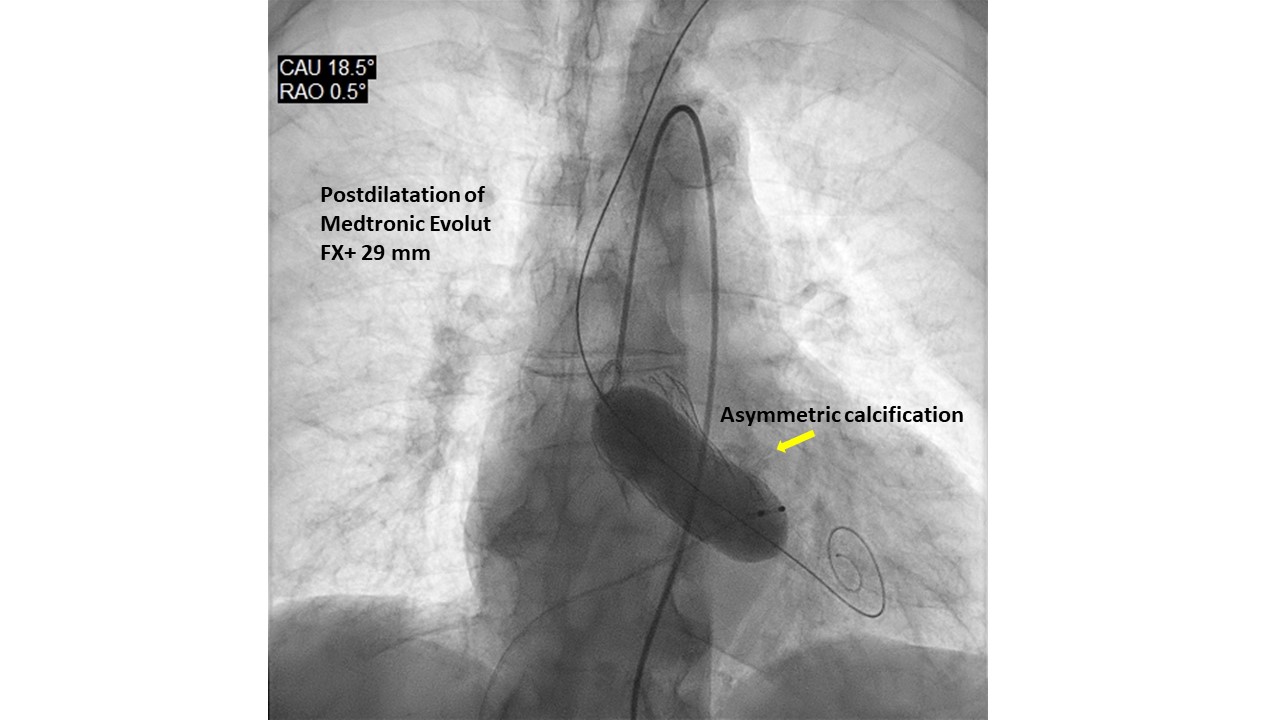

Introduction. Gerbode’s defect dates back to 1857. It generally has a congenital etiology, however very rare acquired forms have been described as complications of cardiac surgery, bacterial endocarditis, thoracic trauma, myocardial infarction or Transcatheter Aortic Valve Implant (TAVI). Diagnosing the communication between the left ventricle and the right atrium post-TAVI is not always easy, but a thorough echocardiography can lead to the correct diagnosis. We present 2 patients with Gerbode's defects post-TAVI, presumed with post-procedural transthoracic echocardiography (TTE) and validated with transesophageal (TEE) or 3D-ultrasound (3DTTE). Methods. A single-centre retrospective study of 1309 consecutive with severe aortic stenosis patients, who underwent TAVI from 2020 to 2025, was conducted with 5 types of aortic valve. All patients were evaluated with TTE before and after the procedure; only 23 patients underwent TEE. Results. Screened patients had a mean age of 82±7 years. Patients had multiple cardiac and non-cardiac comorbidities and high logistic EuroSCOREs and STS scores. Two subjects (0.15%) were found to have a Gerbode-type II septal defect. They were implanted with Medtronic Evolut FX+ valve. The calcium score of the aortic valve annulus was calculated in the 2 patients with CT (3,296 and 2,395 AU, respectively). Both prostheses were postdilated with a balloon to treat residual moderate paravalvular regurgitation. The cases were diagnosed with TEE/3DTTE to have a restrictive left to right shunt (Qp:Qs=1.4 case 1, 1.2 case 2). The patients were not symptomatic and did not require any further intervention. The mechanisms proposed for ventricular septal defect (VSD) formation: pressure exerted directly by the valve on the membranous septum, severe/asymmetric calcification of native valve, aggressive postdilatation. Conclusions. The role of TEE/3DTTE in the accurate diagnosis of these VSD suggests that it can be used as an alternative to other diagnostic tools, such as cardiac catheterization, CT and cardiac magnetic resonance imaging. Gerbode’s defect is a rare complication of TAVI and was detected more with balloon expandable valves, but can also occur with self-expanding ones. Percutaneous treatment was preferred over open cardiac surgery. Some, but not all, patients survived TAVI and VSD, and had a good prognosis for both patient groups with or without VSD closure. Careful follow-up with a dedicated team is essential in these patients.